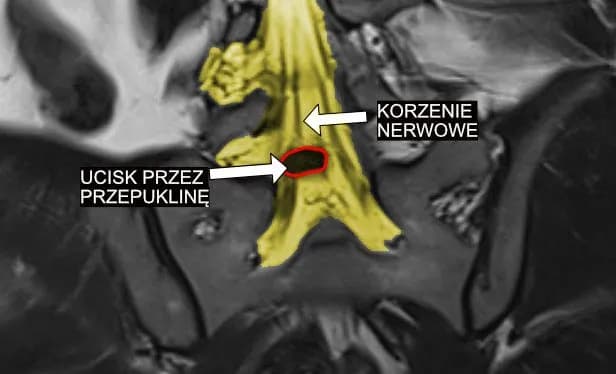

G54 - najpowszechniejsze objawy choroby korzeni i splotów nerwowych

Poznaj objawy choroby oznaczonej symbolem G54 - od wczesnych symptomów po zaawansowane stadium. Sprawdź, czy Twoje dolegliwości mogą wskazywać na zaburzenia korzeni nerwowych.